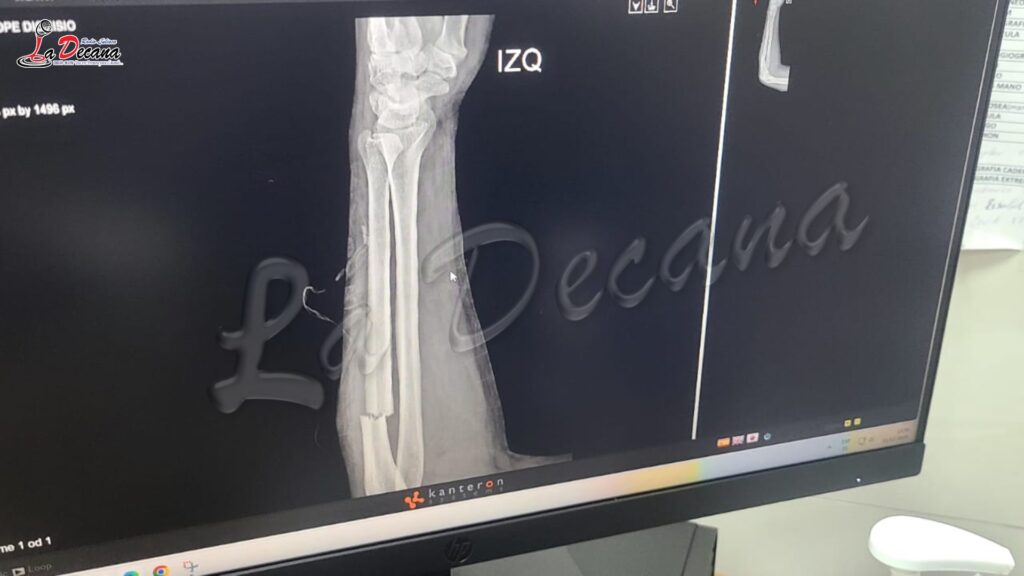

Entre los afectados se encuentra Pedro Ajahuana Tito, jefe de Infracciones del Departamento de Operativos, quien sufrió un corte con exposición de fractura ósea en el antebrazo izquierdo, por lo que fue sometido a una intervención quirúrgica. Asimismo, Candelaria Patricia Huañahui Machaca presentó una presunta fractura del tabique nasal; Lucía Chura Ticona recibió golpes en el rostro y sufrió daños materiales; mientras que Dionisio Churata Lope resultó con un corte en el brazo izquierdo, siendo atendido en el hospital de EsSalud.